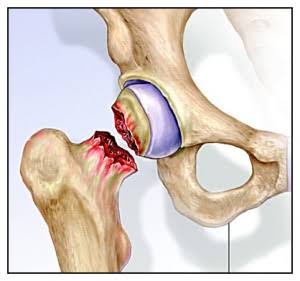

Prótesis Parcial de Cadera

El reemplazo parcial de cadera remueve y reemplaza la cabeza del fémur del paciente, que es la bola en la parte superior del fémur, o hueso del muslo. No reemplaza el encaje. Una bola de cerámica o de metal se adjunta a la parte superior de un vástago que se inserta en el centro hueco del fémur. Los cirujanos suelen realizar esta cirugía para reparar ciertos tipos de fracturas de cadera.